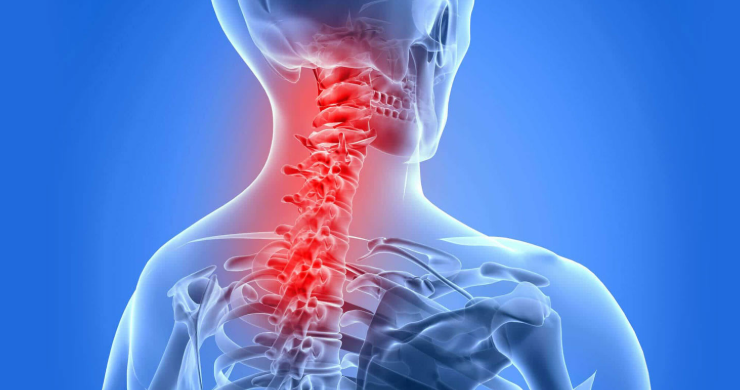

강직성 척추염은 척추를 중심으로 염증이 발생해 점차 뻣뻣해지고 움직임이 제한되는 만성 질환입니다. 이로 인해 목, 허리, 엉덩이 관절 등 여러 부위의 유연성이 떨어지고 일상 동작이 어려워질 수 있습니다. 강직성 척추염 장애등급은 이러한 신체 기능 저하를 사회적 관점에서 평가하기 위한 제도로, 개인의 일상생활 능력과 운동 범위 등을 종합적으로 판단하여 등급을 결정합니다.

X-ray, MRI 등 영상검사는 척추의 강직 정도나 관절 유합 상태를 파악하는 주요 근거입니다. 척추의 변형, 인대의 석회화, 천장관절 손상 등의 유무가 중요하게 평가됩니다.

허리, 목, 골반의 굴곡 및 신전 범위가 얼마나 제한되는지를 측정합니다. 예를 들어, 상체를 앞으로 숙일 때 손끝이 발끝에 닿지 않거나, 고개를 좌우로 돌리는 동작이 제한되는 경우 등이 포함됩니다. 이러한 측정 결과는 기능 평가표를 통해 정량화됩니다.